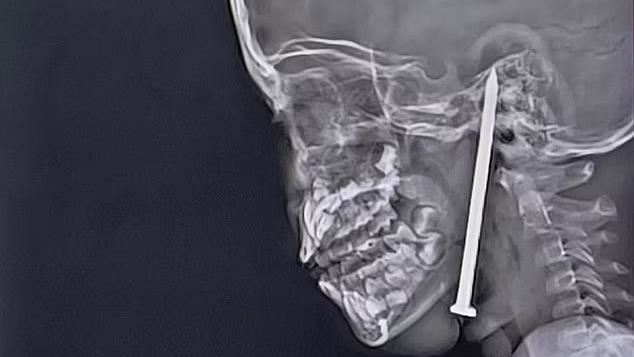

▲印度7歲男童發生意外,一根8公分鐵釘從頸部刺入。(圖/翻攝自X)

印度一名7歲男童日前在玩耍時跌倒,一根長達8公分的鐵釘從頸部刺進腦袋,已經傷及腦部,歷經高風險的10小時手術後,男童奇蹟生還。

報導指出,根據核磁共振和CT掃描顯示,鐵釘刺進了他的頭部,距離主要血管僅剩一點點的距離,情況十分危急,最後透過顯微手術與神經導航技術,順利將這根長達8公分的鐵釘取出。整場手術耗時10小時,手術後男童被送入加護病房觀察,目前狀況穩定、已脫離險境。